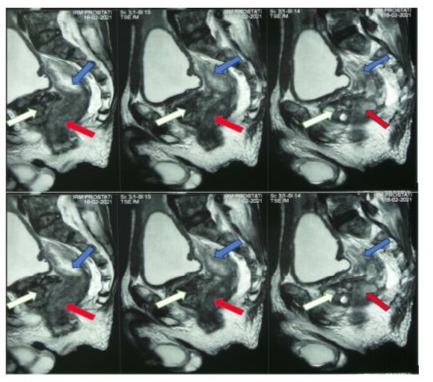

concluded that there was a complete mechanical digestive obstruction by a tumor occupying the entire lumen of the middle rectum with extension to the prostate. The diagnostic hypotheses mentioned were: locally advanced obstructive rectal cancer or prostate cancer with invasion of the rectum. The initial diagnosis was that of an obstructive rectal tumor on preliminary clinical-radiological data. An emergency bowel bypass by a bi-tubular colostomy with biopsy of the rectal mass was performed to diagnostic confirmation. The histopathological examination of the biopsy fragment concluded that adenocarcinoma of the prostate was Gleason 9 (4+5): ISUP 5. (Figure 2).

Figure 2: (HE x10) poorly differentiated acinar adenocarcinoma of the prostate with Gleason score 9 (4+5) i.e. a grade ISUP 5. The tumor architecture is made up of fused glands creating cribriform masses and layers (black star) within a fibromuscular stroma (blue star).

The total PSA performed at 3 weeks postoperatively was 129 ng/ml. A transrectal ultrasound-guided biopsy of the mass was performed after surgery to avoid misunderstanding an associated primary rectal tumor which also concluded that it was a prostatic acinar adenocarcinoma Gleason 9 (4+5): ISUP 5 confirmed with immunohistochemical staining for prostate specific antigen. The extension assessment that was carried out after the histological diagnosis included: